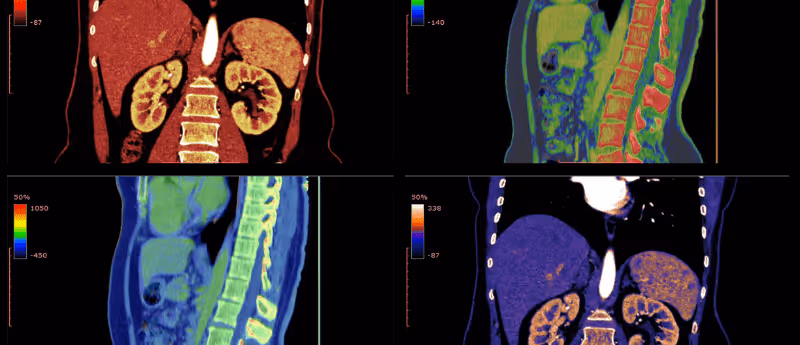

In a recent study, a research team from Pohang University of Science and Technology (Pohang, South Korea) applied a deep learning (DL) technique to photoacoustic computed tomography (PACT) to improve imaging quality. The new approach, termed DL-PACT (DL- enhanced multiparametric dynamic volumetric PACT), enabled the PACT system to image entire bodies of small animals faster and at high resolution. This bears significant improvements to traditional PACT.

The DL network was trained using data from clustered and full view imaging results in order to learn volumetric photoacoustic representations, enabling DL-PACT to generate high-quality structural and dynamic whole body images of small animals in real time. The Pohang University of Science and Technology team were also able to non-invasively monitor dynamic tissue movement at high speed and high resolution in organs, such as the heart and kidney in live animals, and the brain in humans thus overcoming the issue of diffraction-limited resolution in traditional PACT.

Overall, this study is extremely encouraging. DL-PACT represents a whole body imaging technique that is relatively fast and cost effective and one that can be applied to humans, despite training the DL network using animal data. This novel PACT technology can produce high resolution and high speed images without the need for supplementary complex and expensive apparatus, giving it the potential to revolutionize the field of medical imaging in areas such as pharmacology, oncology, cardiology and neurology.